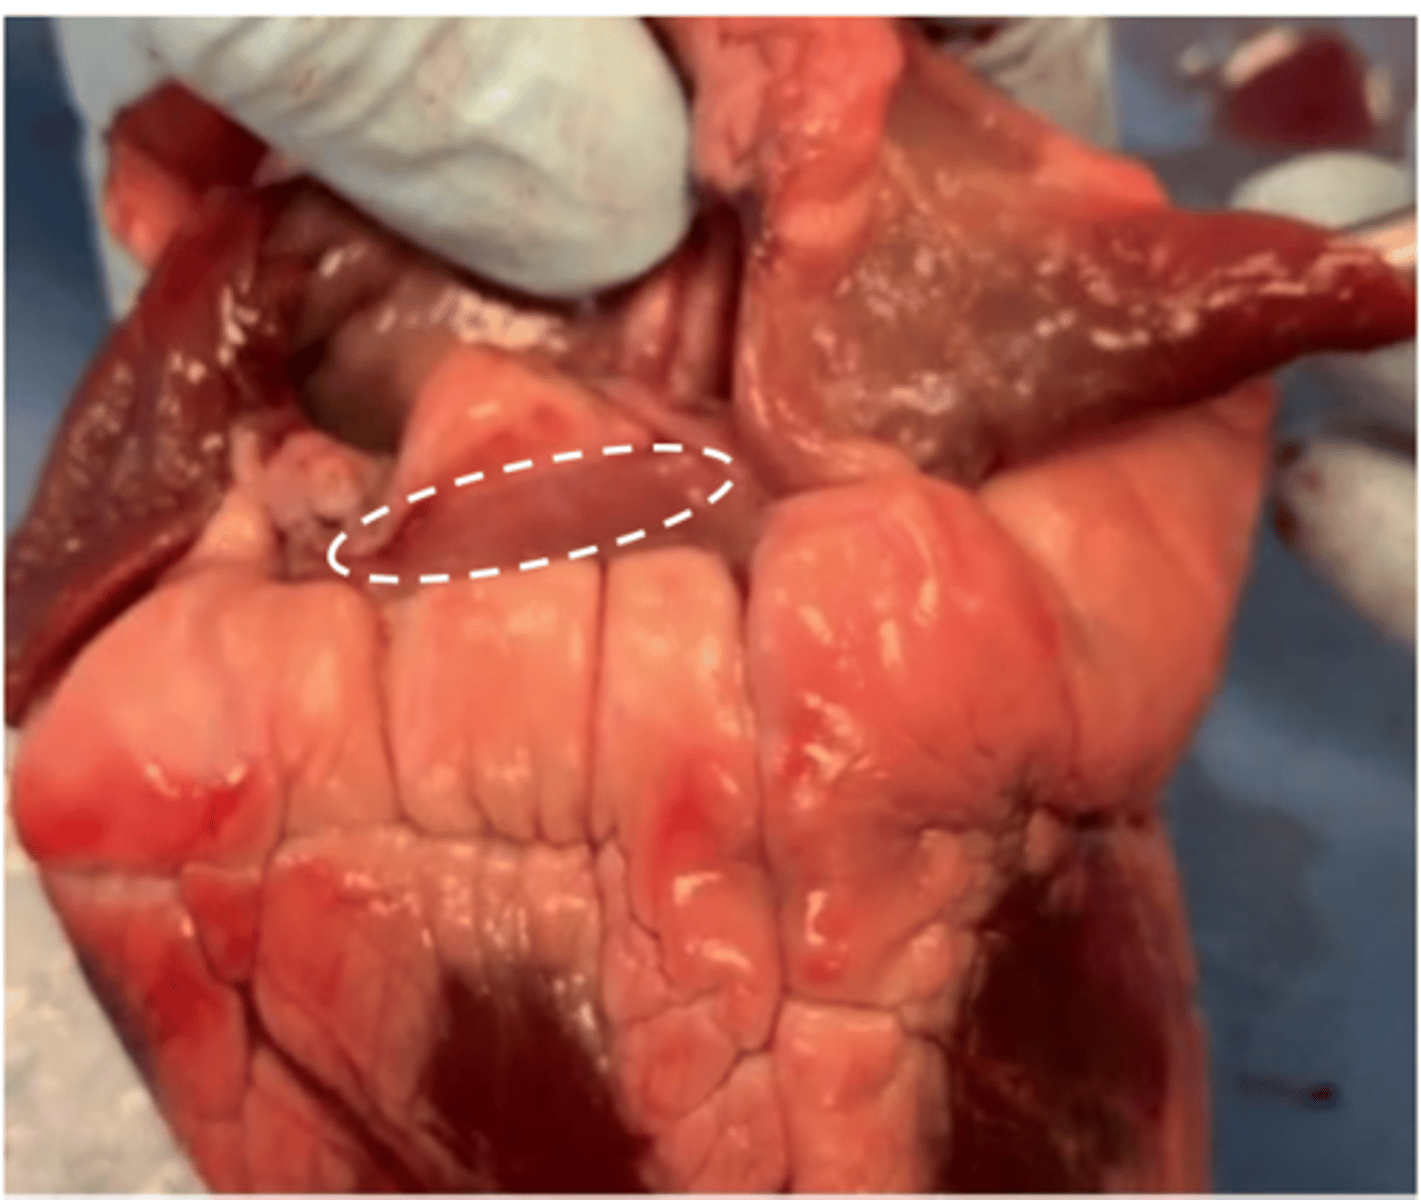

coronary sinus

(can only see on the real model)

<p>(can only see on the real model)</p>